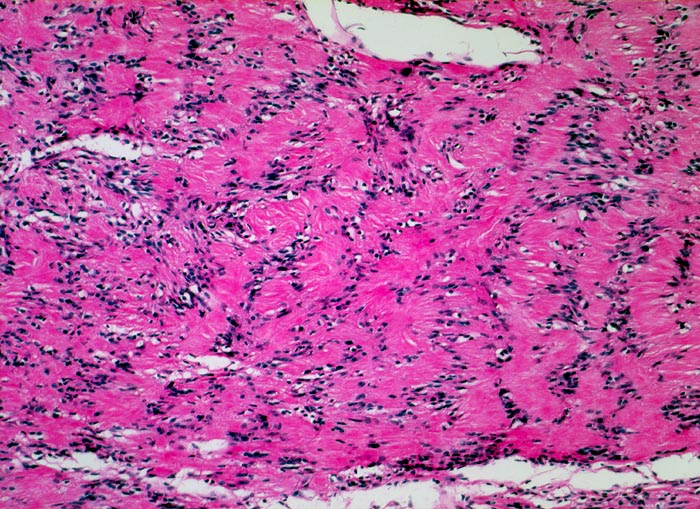

Schwannom: Verocay bodies

Palisadierung der Tumorzellkerne in parallelen Reihen. Dazwischen sind die kernlosen Zellfortsätze ebenfalls parallel angeordnet.

Immunhistochemisch sind die Tumorzellen diffus und stark positiv für S-100 Protein.

Derber abgekapselter Tumor am Nervus ulnaris

Die parallele Anordnung von Zellkernen und Zytoplasmafortsätzen nennt man Verocay body. Diese sind typisch für Schwannome können aber auch von anderen Tumoren imitiert werden (z.B. Meningeom).

100